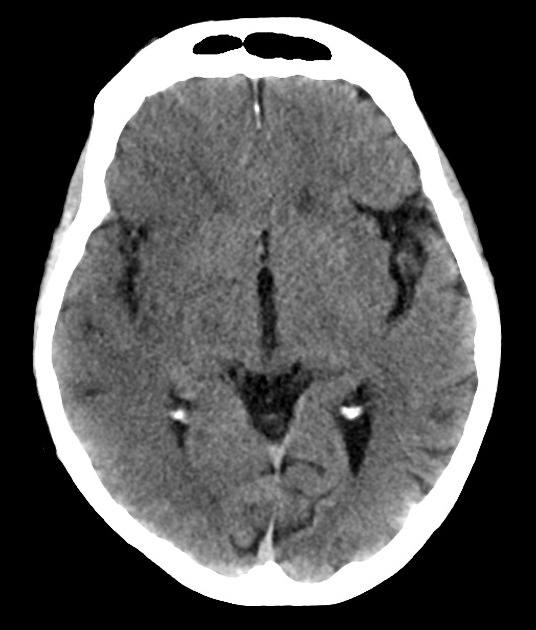

Nhồi máu não

» Thông tin: Nam giới – 60 tuổi.

» Lâm sàng: Đau đầu + Liệt nửa người trái / NIHSS 18 điểm.

# Nhồi máu sớm bán cầu phải thuộc vùng cấp máu ĐM não giữa / Huyết khối ĐM não giữa phải.